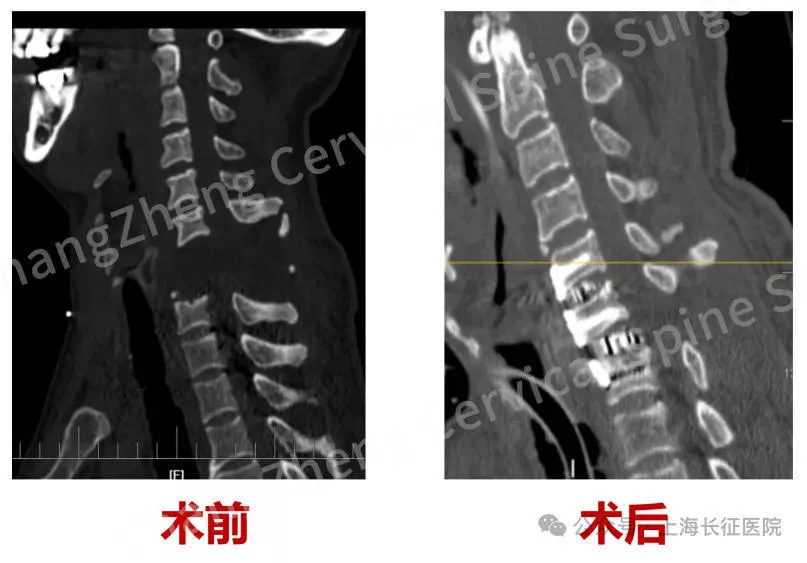

据了解,“身首离断”式的颈椎大跨度脱位本就罕见,成功复位更是闻所未闻。术前影像学检查显示,患者脊髓严重挫伤、关键的神经血管结构撕裂。

▲术前、术后影像对比 图据医院

8月18日,这台手术的主刀医生之一,上海长征医院骨科副主任、颈椎外科病区主任陈华江告诉红星新闻,患者是6月18日进行的手术,目前生命体征稳定,已脱离呼吸机大概半个月。患者双下肢功能永久损伤无法挽回,挽回性命已实属不易,上肢功能在逐渐锻炼康复中。